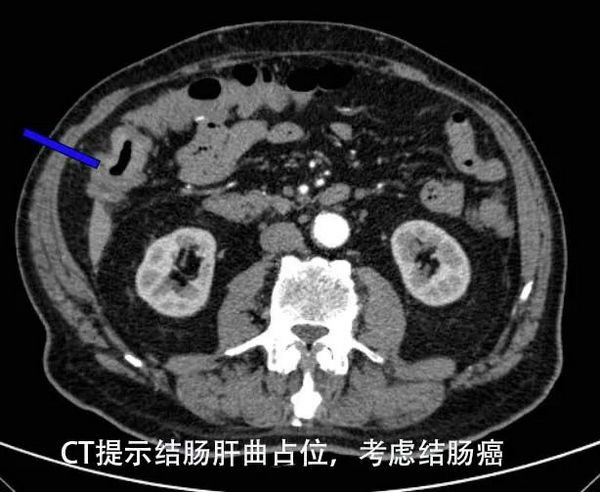

近日,90岁高龄的王老师突然晕倒了,他患有多年的高血压和冠心病,家属急忙将他送到一直体检保健的郑州大学五附院心内科。住院后患者又突发心跳骤停,在高质量心肺复苏抢救后,心脏跳动恢复,经过几天的救治病情基本稳定。但患者心绞痛、头晕发作是因为“重度贫血”,进一步肠镜检查发现“真凶”是藏在肚子的“炸弹”——结肠肿瘤。经“输血、改善心脏功能“等对症治疗后,老爷子头晕、心脏不适较前好转,可仍然合并黑便及腹胀症状。好不容易输的血一直因为肿瘤出血而流失,一时的好转还是不能去除根本病因,家属对此忧心忡忡。在了解郑州大学五附院胃肠甲状腺外科技术力量雄厚后,为真正挽救王老师的生命,带着满心的期待,家属找到胃肠外科专家杨战锋主任。

11月23日,患者转入胃肠外科,经全院多学科会诊、科室疑难病例分析及术前讨论,全面综合评估患者年龄、身体状况等因素后,制定了经腹腔镜微创的手术方案。11月26日,由杨战锋主任主刀,在手术麻醉科的全力保障下,历时2小时,在“快、准、精”的原则下,成功实施“腹腔镜下结肠癌根治切除术”,术后3天开始饮食,术后1周患者康复出院,再未出现头晕不适,连困扰几十年的便秘、肚子胀的症状也一朝解除。出院之际,家属激动不已,对杨战锋主任和郑州大学五附院医护团队的精湛医术与精心照护表示感谢!